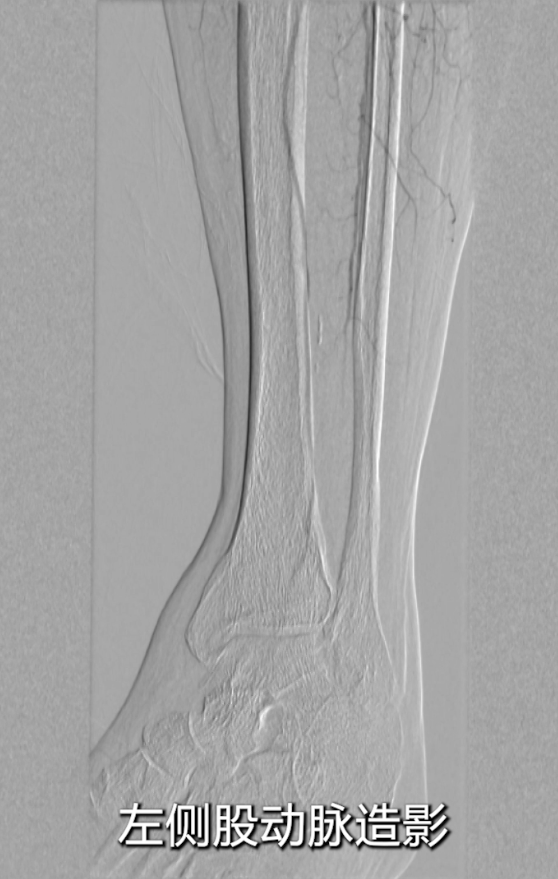

采用右侧股动脉入路,穿刺股总动脉后行基线造影;

腹主动脉及左侧股动脉造影显示:左侧股总动脉支架几乎完全闭塞,

支架长度较长(从股总动脉延伸至收肌管临近P1段),且部分遮挡股深动脉开口;膝下动脉显影稀疏,流出道条件差。